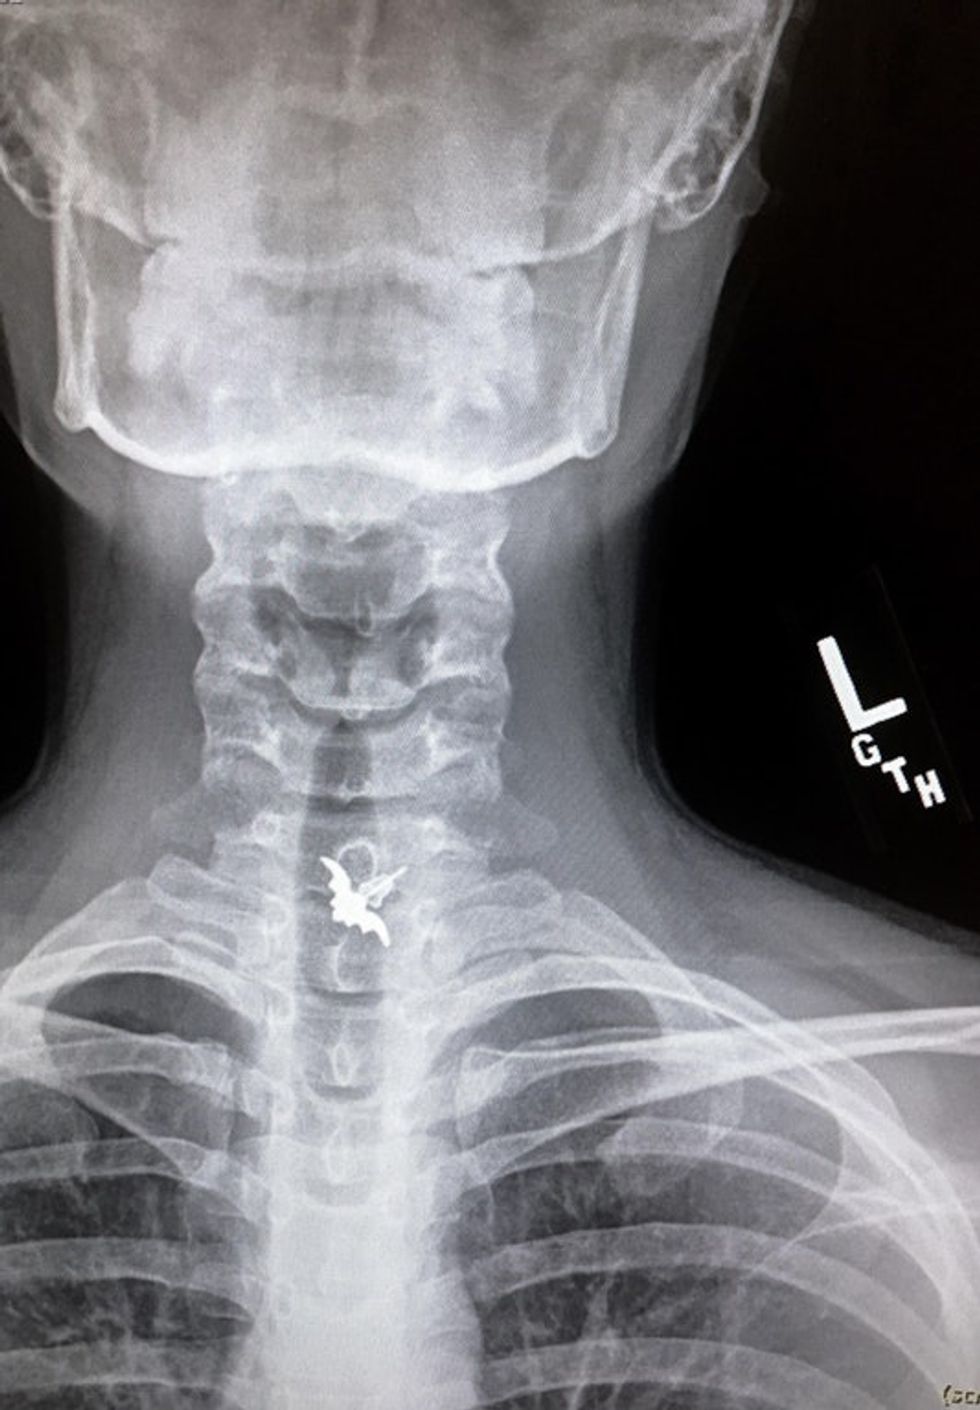

Emdarko then offered up even more X-rays and photos from before and DURING her operation: